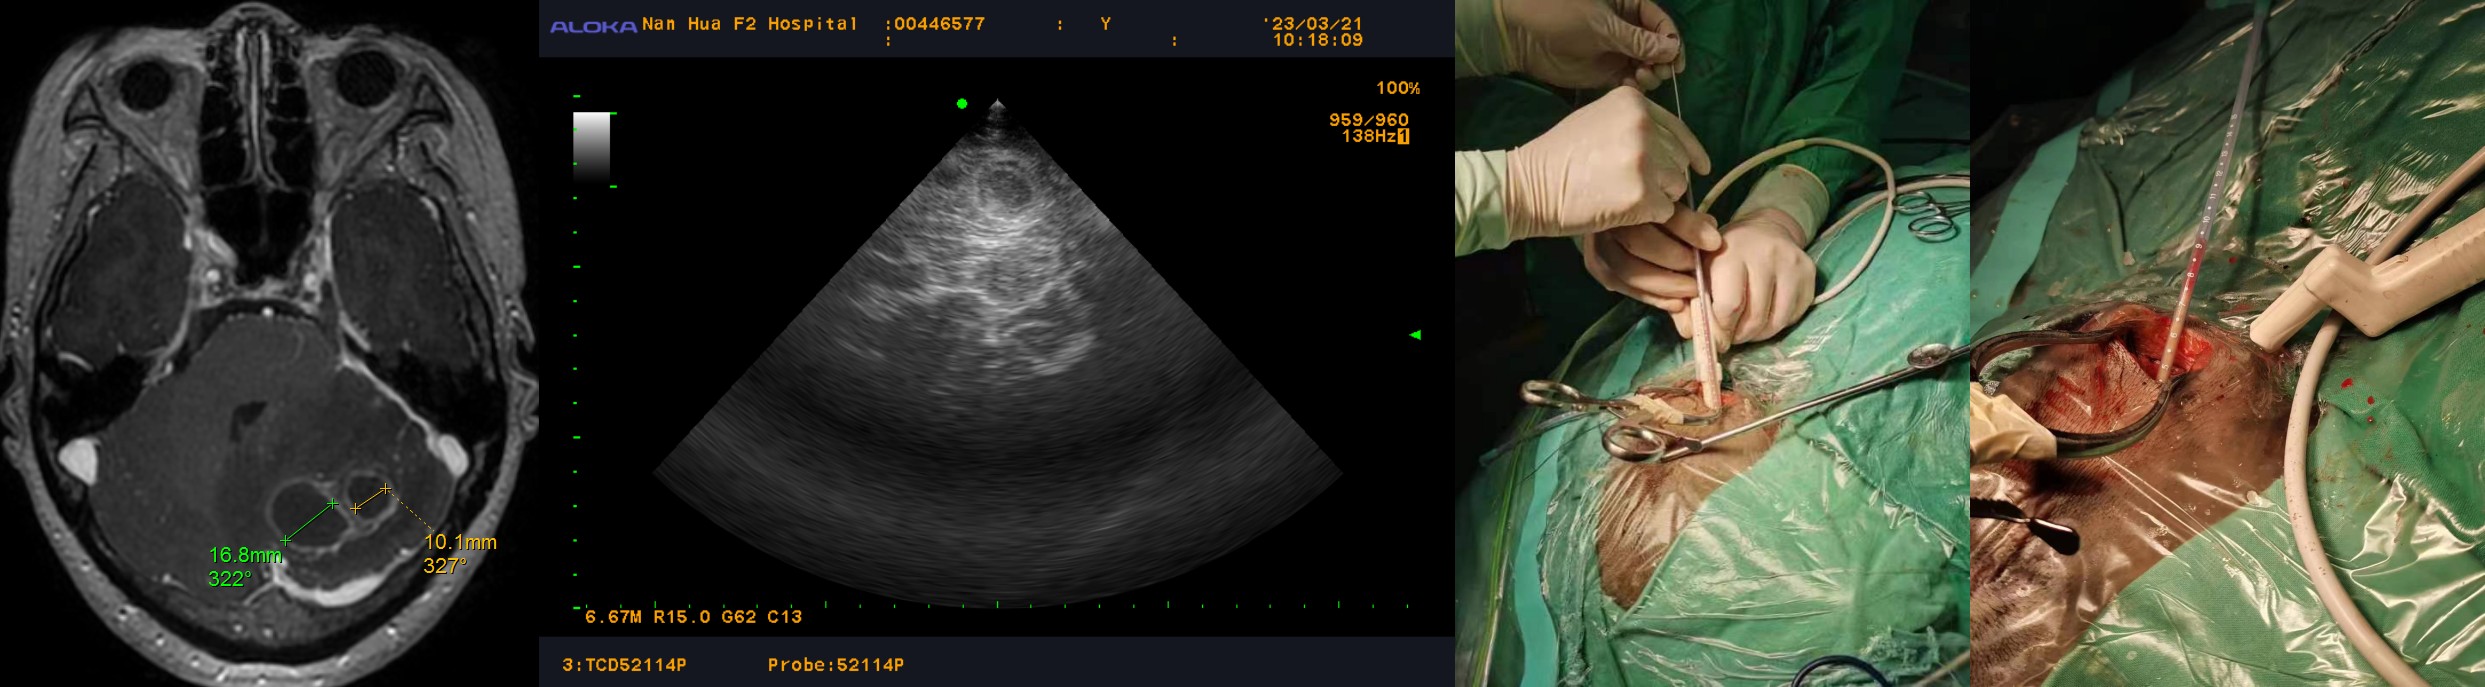

拟全麻下行脓肿穿刺引流术。

3月21日在全麻下行脓肿穿刺引流术。

由于两个脓肿腔均较小,直径分别为1.6cm,1.0cm,术中使用B超引导双通道穿刺引流,术中抽吸脓液,并甲硝唑盐水反复灌洗。